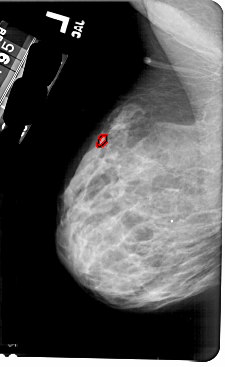

A_1797_1.RIGHT_CC

RIGHT_CC LINES 5146 PIXELS_PER_LINE 2986 BITS_PER_PIXEL 12 RESOLUTION 43.5 NON_OVERLAY

FILE: A_1797_1.LEFT_CC.OVERLAY

TOTAL_ABNORMALITIES 1

ABNORMALITY 1

LESION_TYPE CALCIFICATION TYPE PUNCTATE DISTRIBUTION CLUSTERED

ASSESSMENT 4

SUBTLETY 2

PATHOLOGY BENIGN

TOTAL_OUTLINES 1

BOUNDARY